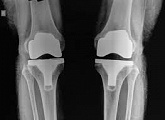

Еndoprosthesis of knee joint

In the late stages of arthrosis of the knee joint, accompanied by a pronounced restriction of the volume of movements, constant intense pain, deformity of the limb, the only way to recover is to replace the affected joint with an artificial joint - arthroplasty.

This method allows you to return the correct form of the limb, the full volume of movements in the joint, relieve the constant pain and crunch during movements and, as a result, significantly improve the patient's quality of life.

Below are presented X-ray photographs and photographs, illustrating the amount of motion in the affected joint before and after surgery.